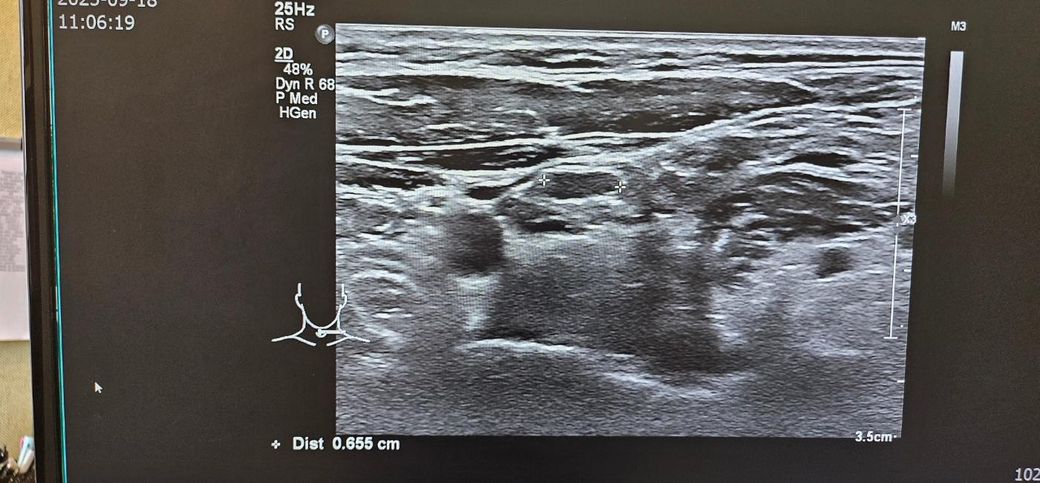

경부초음파 자세하게 설명좀 부탁드립니다

통증이있어서 초음파했는데

약먹고 통증은 없습니다

초음파 보시고 자세히 설명좀 부탁드립니다..

• 2번 째 사진